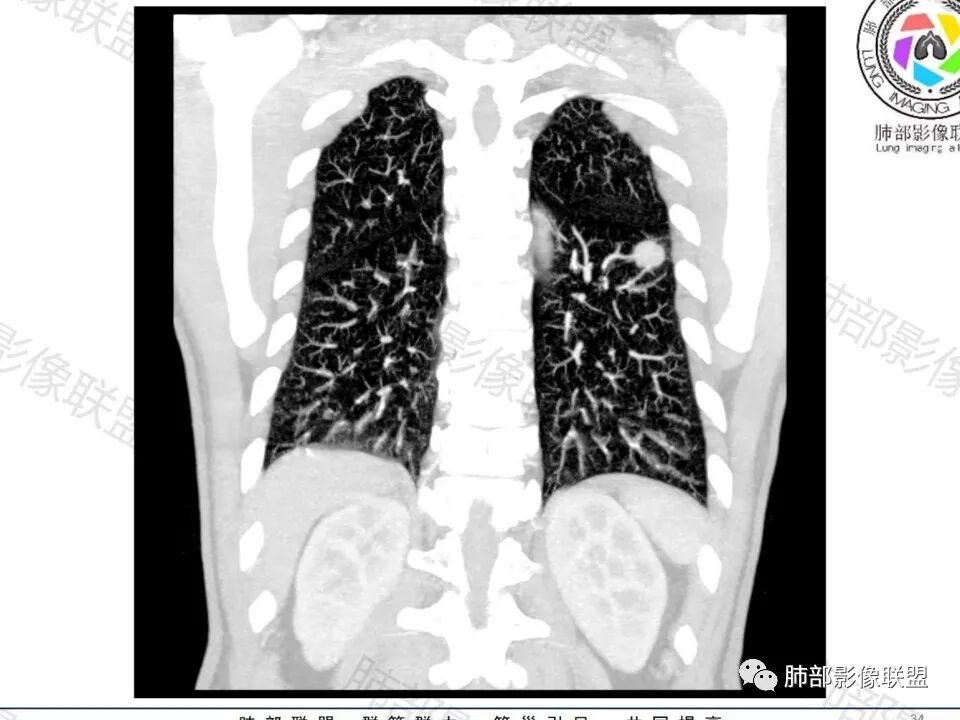

左下肺、右中肺均有结节,左下肺病灶比较鼓,边缘有晕,血管弯,持续性强化,考虑腺癌可能,鉴别两处病灶如果一元论,肉芽肿炎 (隐球)

图做的真漂亮!老年男性,双肺多发结节,最大者位于左肺下叶胸膜下,周围有晕,晕中毛刺,边缘有一囊腔,胸膜牵拉,持续强化,考虑隐球,鉴别腺癌。

左肺下叶胸膜下类圆形结节,边缘光滑,周围有晕,晕中有毛刺,周围可见小卫星灶,相邻胸膜增厚,血管进入,右肺中叶可见小结节影,考虑炎性肉芽肿,隐球菌。鉴别腺癌。

老年男性,左肺下叶背段胸膜下结节,边缘毛刺,血管进入,斜裂有牵拉,局部胸膜糊墙,周围有晕,但有一囊腔,首先考虑腺癌,但是右肺中叶及左肺下叶还有其他结节,鉴别隐球菌

多发类似结节

1、炎性结节,多发,类似,晕,隐球菌?

2、恶性:多发:转移瘤?肺癌并多发转移瘤?